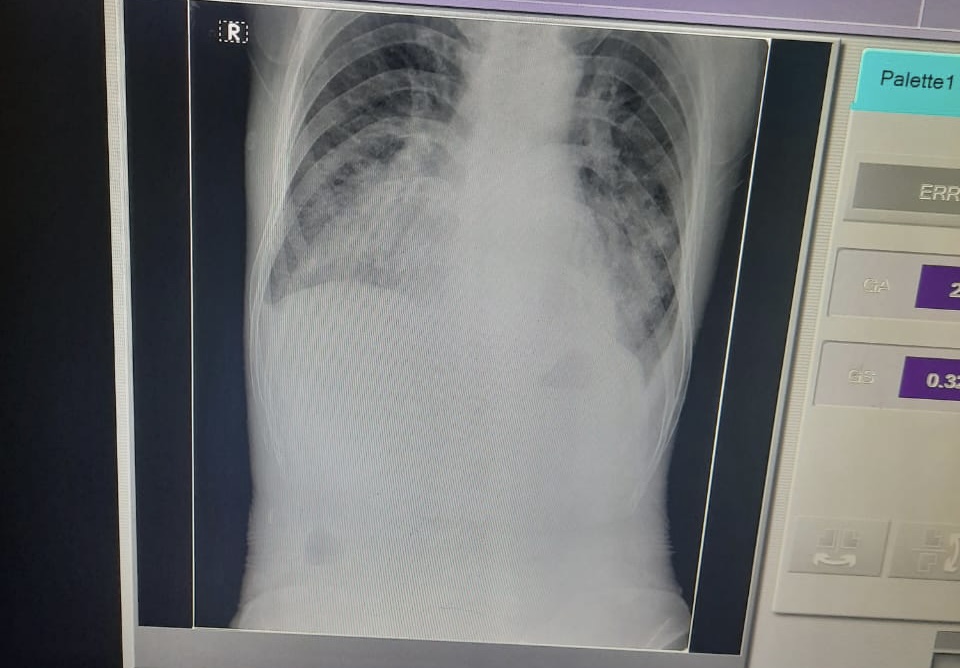

Chest x-ray :